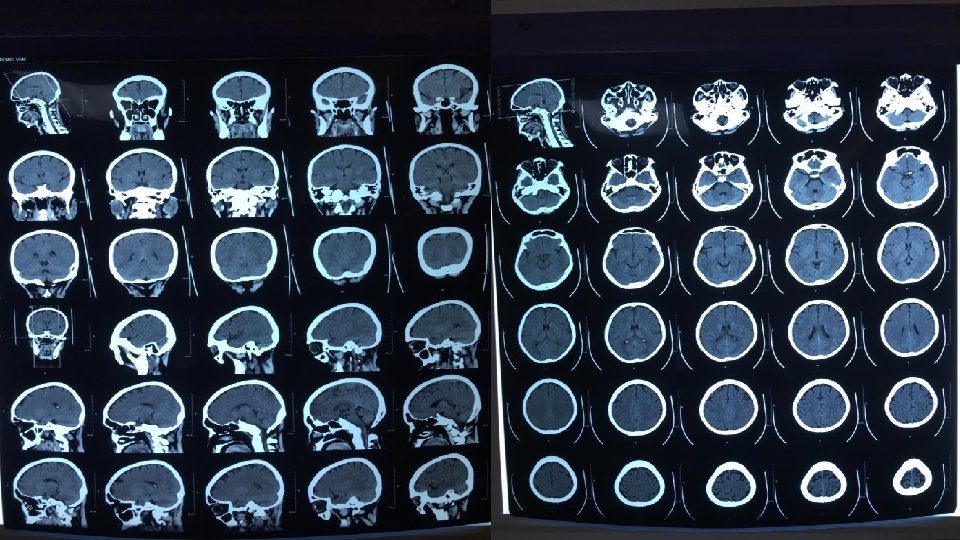

HCTS (15 Mei 2019) Hasil : • Tak tampak soft swelling extracranial, Sistema tulang normal, SPN dan air cellulae mastoidea normal. Sulci dan gyri mulai prominent, batas cortex dan medulla tegas, Sistema ventrikel simetris, ukuran melebar, tak tampak edema periventrikuler. Struktur mediana di tengah, tidak terdeviasi. Kesan : • Tak tampak kelainan